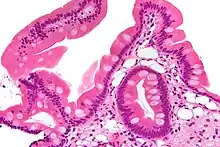

| Low magnification micrograph of Whipple's disease showing the characteristic foamy appearing infiltrate of the lamina propria. Duodenal biopsy. H&E stain. | |

Endoscopy of the duodenum and jejunum can reveal pale yellow shaggy mucosa with erythematous eroded patches in patients with classic intestinal Whipple's disease, and small bowel X-rays may show some thickened folds. Other pathological findings may include enlarged mesenteric lymph nodes, hypercellularity of lamina propria with "foamy macrophages", and a concurrent decreased number of lymphocytes and plasma cells, per high power field view of the biopsy.